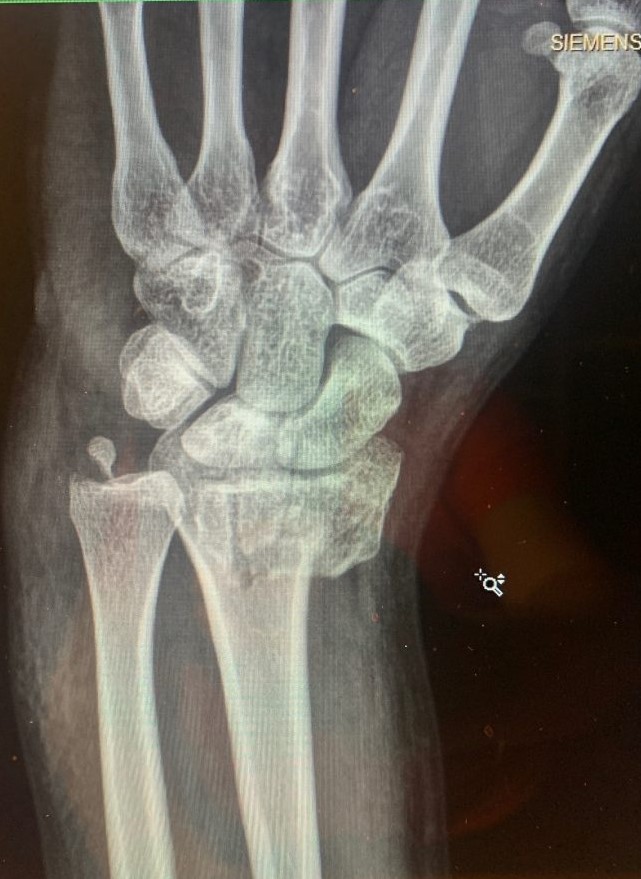

It all happened in a flash: I was biking on a warm Friday afternoon before Labor Day and all of a sudden I hit a pothole. I found myself lying in the street in agonizing pain with my left wrist tremendously swollen. At the emergency room, the doctors set my wrist somewhat in place and placed me in a cast up to my bicep. But they told me that I needed to have my wrist examined very soon (see photos 1, 2 and 3).

In the recovery room after surgery, Dr. Daluiski said that everything went well, even though it was a very severe accident. He inserted multiple plates and screws to help set my wrist (see photo 4). It was pretty painful for 2-3 days after surgery, but after that my wrist began to feel progressively better. I saw Dr. Daluiski about one week after the surgery and he said everything looked great so far (see photo 5 and 6). I was amazed that my wrist began to look like a normal wrist and that I was able to begin performing gentle range of motion exercises with the occupational therapists at the hospital. About six weeks after the surgery, I had a second surgery to remove some of the hardware in my wrist. The second surgery also went very smoothly. Throughout this process, I continued working with the occupational therapists to regain the motion and strength in my wrist.